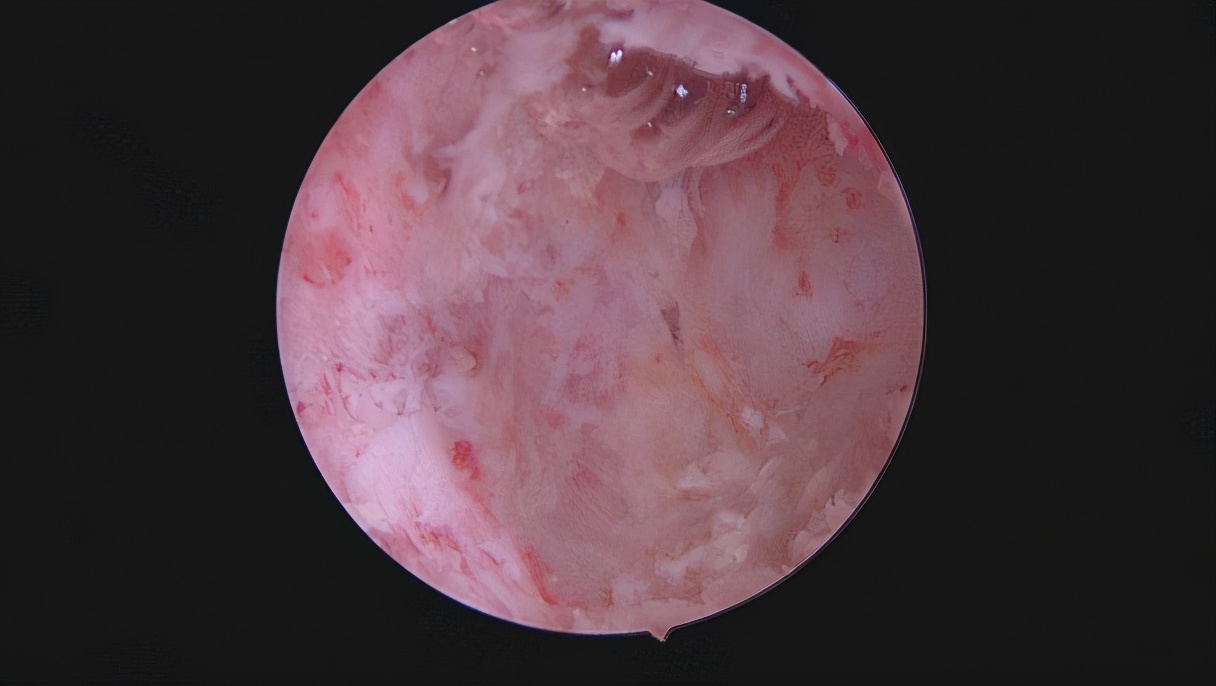

重度宫腔粘连术前图片

图一:宫腔疤痕